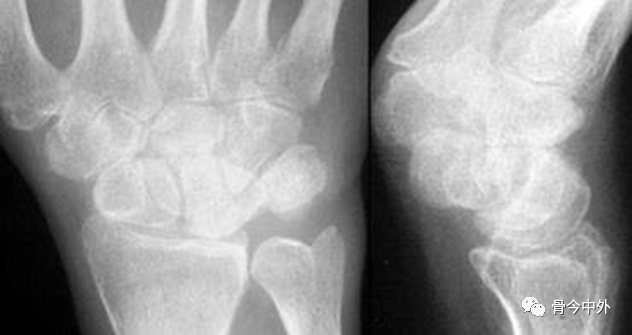

图2 成人期腕关节正侧位及舟骨蝶位片。1.舟骨;2.月骨;3.三角骨;4.豆状骨;5.大多角骨;6.小多角骨;7.头状骨;8.钩骨;9.桡骨茎突;10.尺骨茎突;11.第一掌骨基部。

图3 成人期腕关节正侧位及舟骨蝶位片。12.舟骨结节。黑色箭头:舟骨腰部;白色箭头:舟骨滋养血管影。